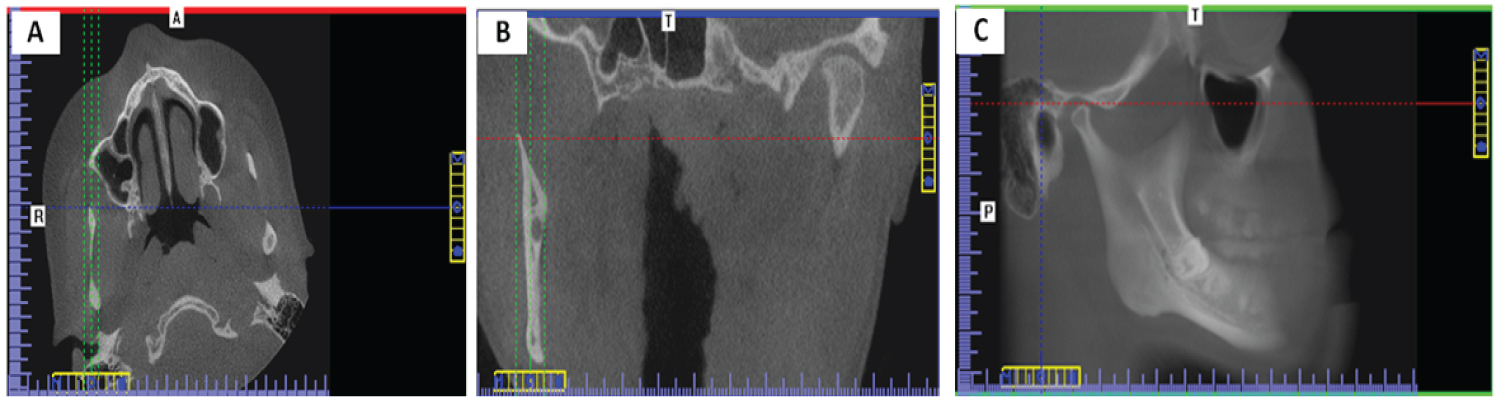

To measure distance MFD, In the coronal view, the axial plane was scrolled till the slice just before which the foramen is completely surrounded by bony cortex. In the axial view, the view was rotated till MF buccal wall became parallel to sagittal plane, then the distance from the lingual to the buccal border of the mandibular foramen was measured as illustrated in (Figure 3A). (Figure 3B) illustrates measurement of MFD from the standardized sagittal view.

Figure 3: A) Standardization of axial view on I-CAT Vision software to measure MFD. The axial slice just before the mandibular foramen was completely surrounded by a bony cortex was rotated till the buccal wall of the MF became parallel to the sagittal view; B) Measurement of Depth of the mandibular foramen MFD in a forty-three-year-old dentate female on I-CAT vision software. View Figure 3

To measure distances MF-OP and MF-ARMT, In the coronal view, the axial plane was scrolled up to the slice that shows the widest pulp chamber of the mandibular first molar. In the axial view, the view rotated till the buccal wall of mandibular six parallel to sagittal plane, then the sagittal plane was moved to pass through the lingual wall of the mandibular first molar and also bisect the mandibular ramus as illustrated in (Figure 4A). In the axial view, the coronal plane was scrolled up to the first slice that shows the mandibular foramen completely surrounded by cortical bone. In the coronal view, the view was rotated till MF lingual wall parallel sagittal plane, then the sagittal plane was moved to pass through the lingual wall of the mandibular foramen as well as the mandibular condyle as illustrated in (Figure 4B). (Figure 5A and Figure 5B) show measurement of MF-OP and MF-ARTM from the standardized sagittal view.

Figure 4: A) Standardization of the axial view on I-CAT Vision software to measure MF-OP and MF-ARMT. The axial view that showed the widest pulp chamber of the mandibular first molar was rotated till the buccal aspect of mandibular first molar became parallel to the sagittal plane. The sagittal plane was then moved to pass through the buccal wall of the mandibular first molar and also bisect the mandibular ramus; B) Standardization of the coronal view that showed the mandibular foramen completely surrounded by cortical bone. The coronal view was rotated till the condyle processes and lingual wall of the MF became on the same plane, and the sagittal plane was moved to pass through the lingual wall of the mandibular foramen as well as the mandibular condyle. View Figure 4